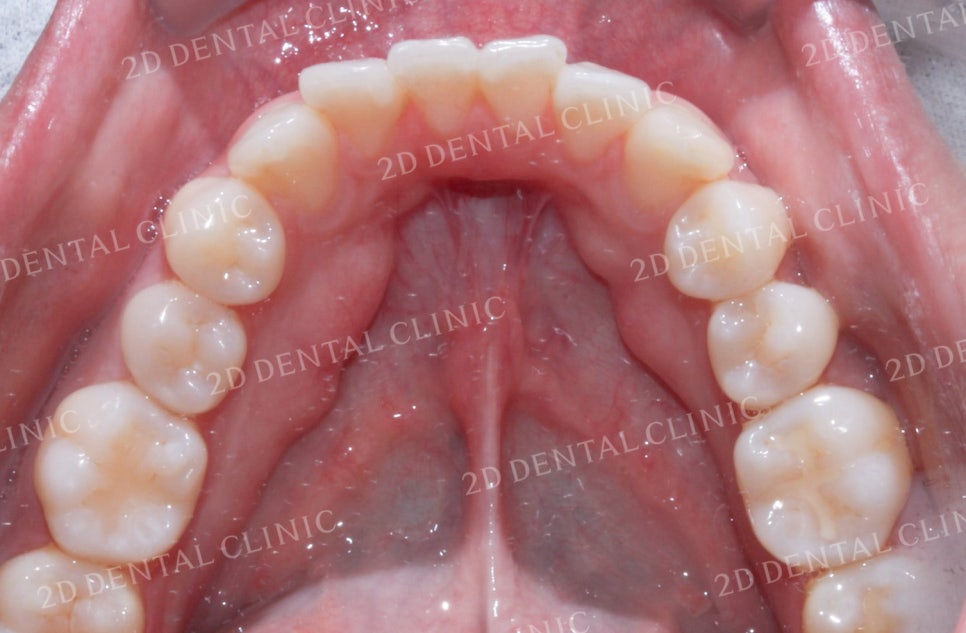

<Before> <After>

비대칭앞니, 돌출앞니를 전체교정으로 교정하고 싶다면!? by.투디치과(2D치과)

상악의 설측면 교정치료 전후 사진입니다.

돌출과 총생으로 삐뚤거렸던 앞니가

교정 후 올바르게 정리된 모습입니다.